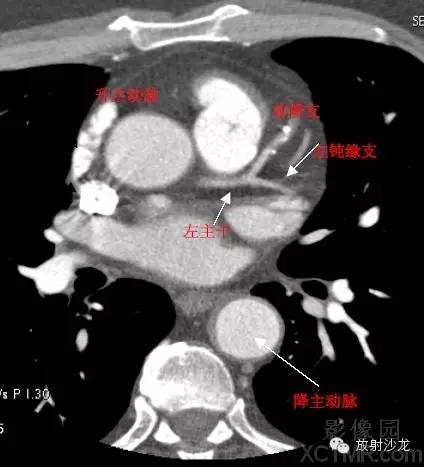

A.Aorta-Ascending Aorta升主动脉

D. Aorta-Descending Aorta降主动脉

LMA -Left Main Artery冠状动脉左主干

LAD -Left Anterior Descending Artery左前降支

LMB -Left Obtuse Marginal Branch 左边缘支(钝缘支)

RCA -Right Coronary Artery 右冠状动脉